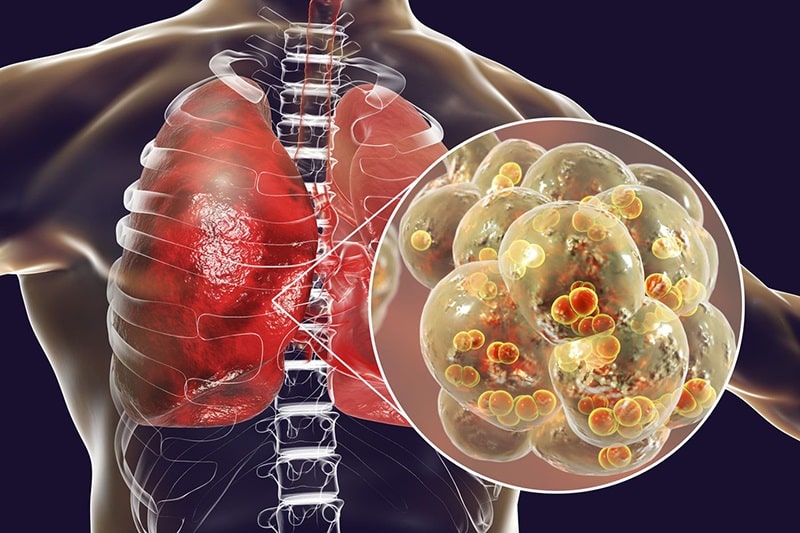

Bệnh lý về phổi

Đau lưng khó thở cũng là một trong những dấu hiệu của các bệnh lý về phổi như viêm phổi. Tình trạng viêm phổi xảy ra do nguyên nhân nhiễm trùng ở các nhu mô phổi, cảm lạnh và thường có thể phục hồi nhanh chóng, không biến chứng. Tuy nhiên nếu để bệnh diễn tiến nặng thì người bệnh sẽ bị đau lưng, khó thở và đau đớn hơn khi ho.

Đau lưng khó thở là bệnh gì? Dấu hiệu của các bệnh lý về phổi

Đau lưng khó thở do tắc nghẽn phổi

Tình trạng tắc nghẽn phổi cũng có triệu chứng đặc trưng như đau lưng hay khó thở. Khi người bệnh bị tắc nghẽn phổi sẽ gặp khó khăn trong việc hít thở, luôn cảm thấy đau nhức lưng, ho nhiều có đờm và đôi khi thở dốc bất thường,… Tình trạng tắc nghẽn phổi không nên kéo dài và nếu để tiến triển thành mãn tính sẽ gây biến chứng ảnh hưởng tới hệ thần kinh, tim mạch.